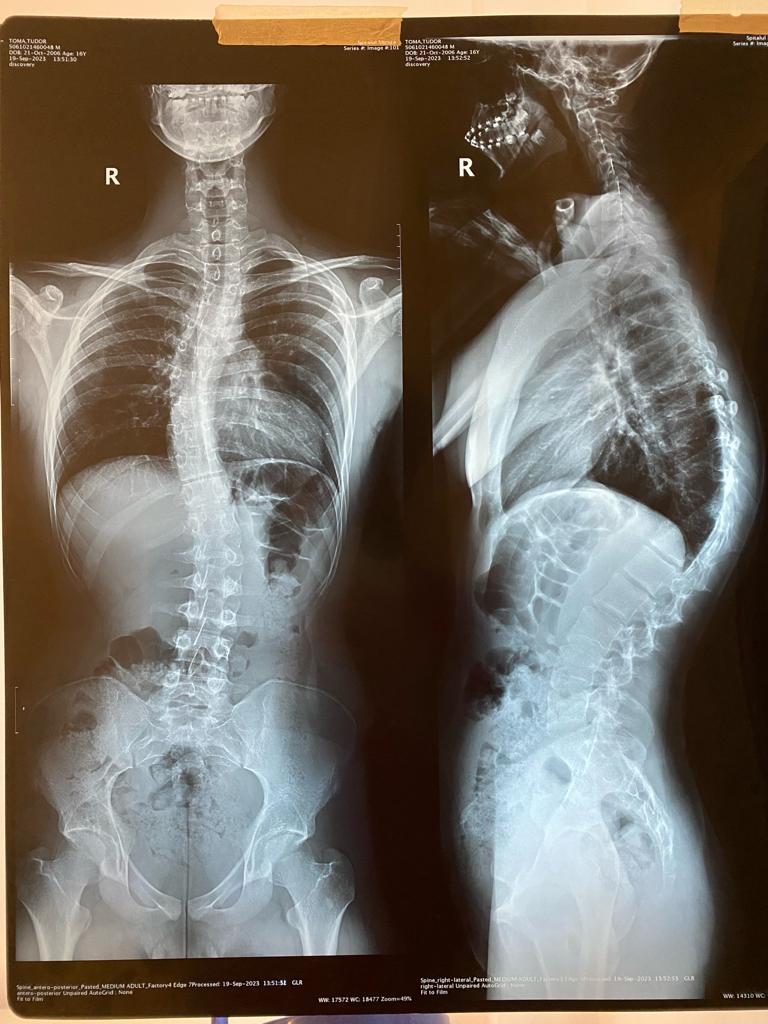

Pentru un elev eminent de la Liceul Sf. Sava din Capitală statul în bancă a devenit un calvar. O afecțiune gravă a coloanei vertebrale îi provoacă dureri cumplite.

„Orice mișcare pe care o fac a devenit chinuitoare. Chiar și simplul fapt de a respira îmi provoacă dureri. Nu pot sta foarte mult pe scaun. Din cauza presiunii la care e supusă coloana mea, cu o curbură de 70 de grade, statul în bancă a devenit un coșmar."

În ciuda tratamentele, starea de sănătate a tânărului s-a deteriorat rapid. Adolescentul are nevoie de o intervenție chirurgicală complexă la Spitalul Monza din București. Operația, esențială pentru a-i oferi lui Gabriel șansa la o viață normală, implică tehnologie avansată și materiale costisitoare, cum ar fi tije din titan. Intervenția costă peste 24.000 de euro.